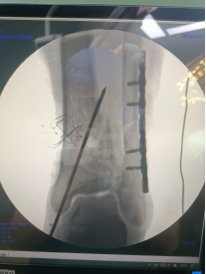

腓骨予以重建內(nèi)固定板固定。

三臂十一軸機(jī)器人輔助器牽引,安裝外固定架,透視檢查骨折端對位對線良好。